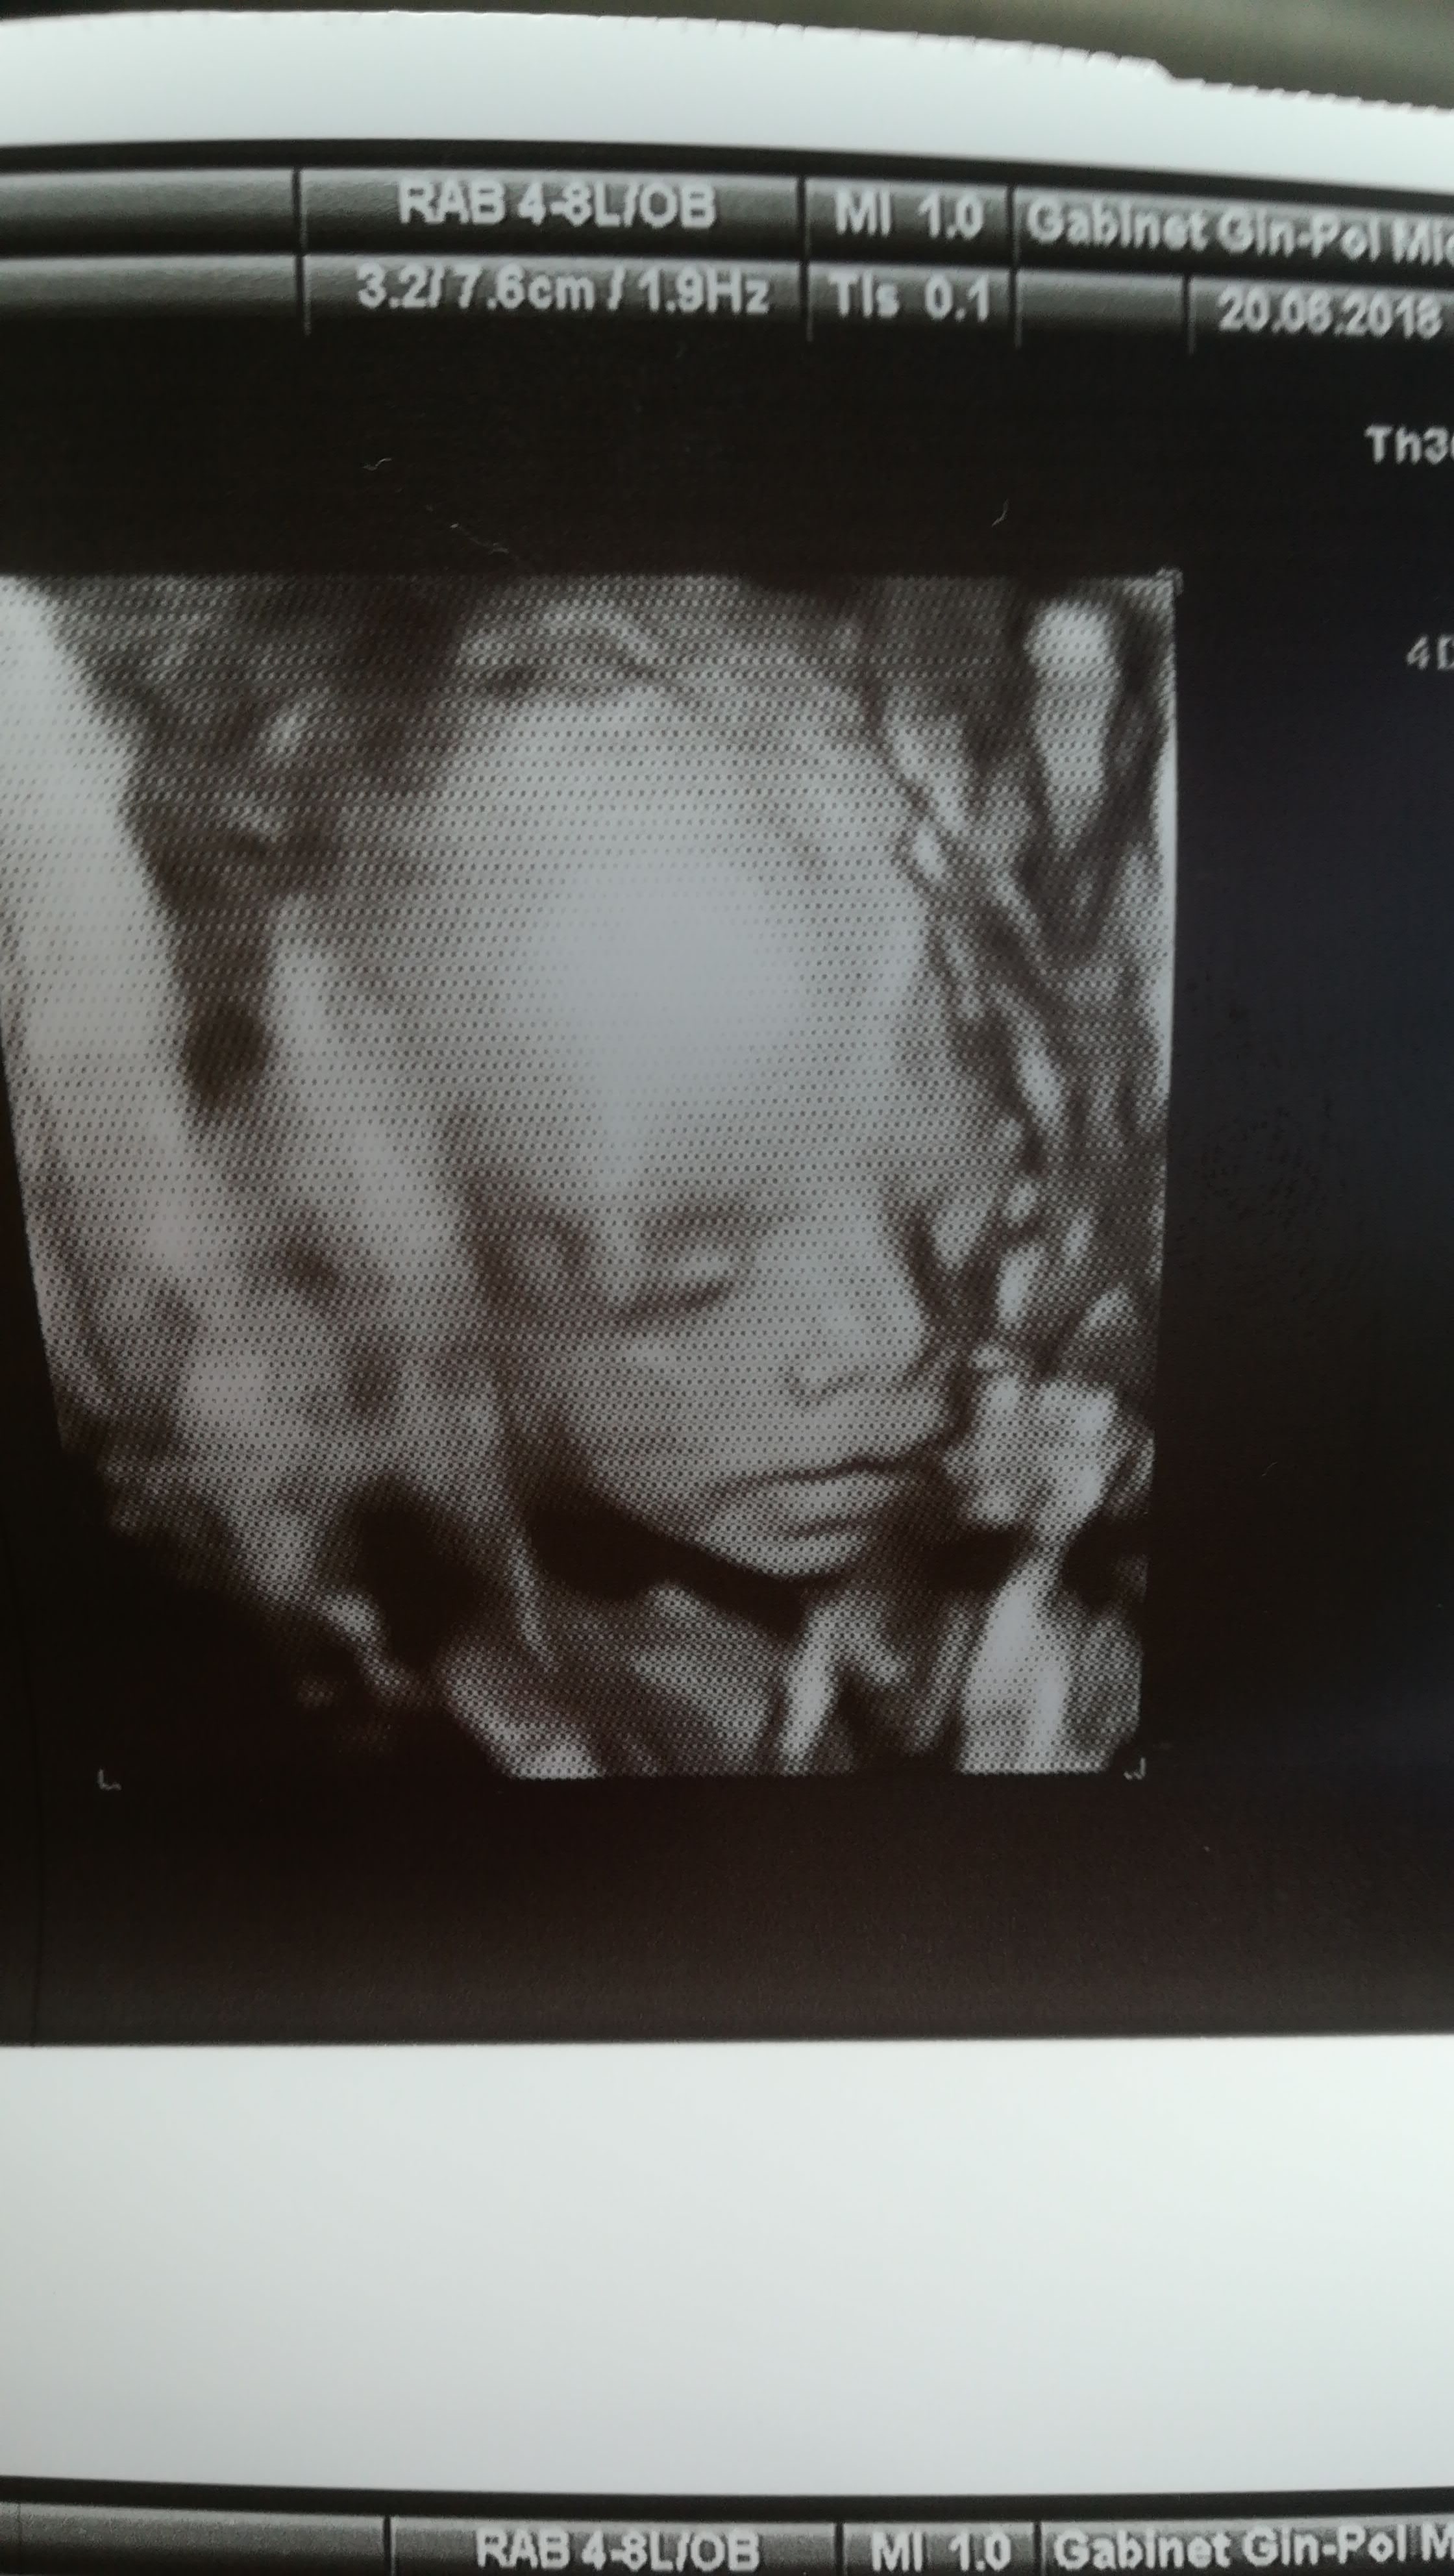

Szczypiorkowa! pobuzi widać cudna dziewczynę [emoji177] Gratulacje dla was. Oszczędzaj się i nigdy nie mów nigdy [emoji6] bo nadal jesteście młodzi i wszystko może się stać [emoji846]